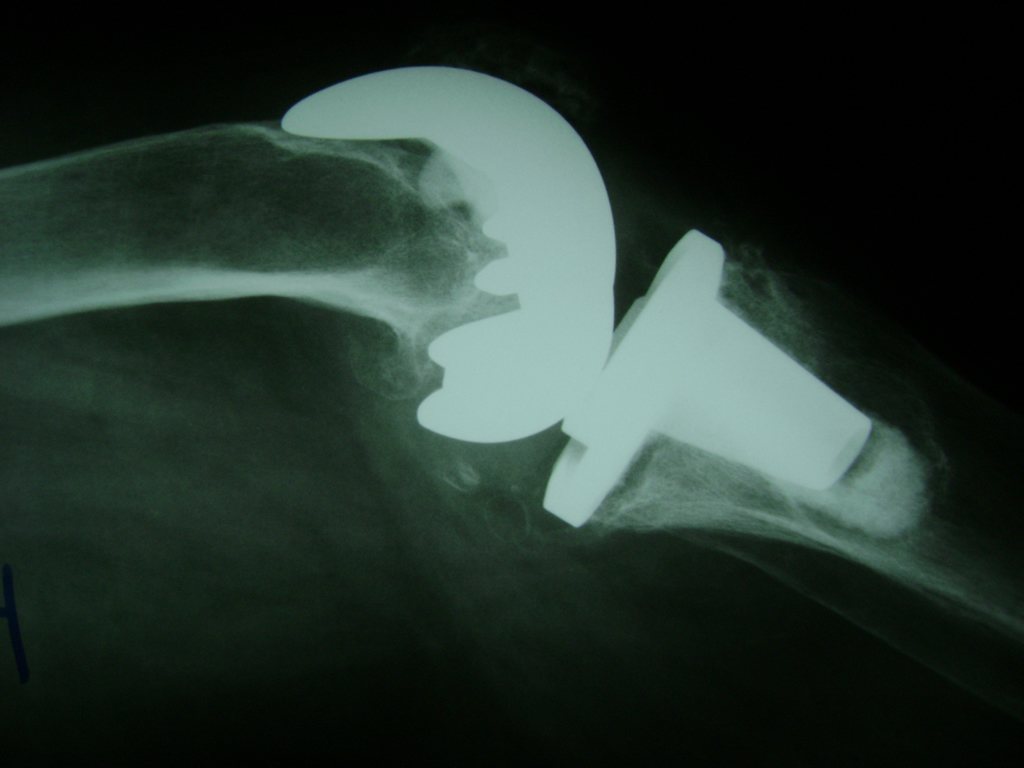

La artroscopia de rodilla es un cirugía en el cual la estructura interna de la articulación es examinada ya sea para realizar un diagnostico o para realizar un tratamiento, este procedimiento se realiza utilizando un instrumento parecido a un pequeño tubo llamado artroscopio.